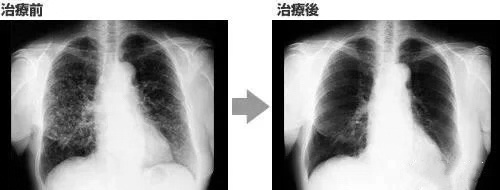

案例 2:国内一名 60 岁的卵巢癌晚期患者,在接受了体外扩增、高度活化的同种异体 NK 细胞的治疗后,CA125 水平从 11,270 降至 580,所有腹水都消失了。此外,CT 扫描的肿块体积减小,并且没有出现副作用。 案例 3:一名广泛期小细胞肺癌患者,在进行 4 个疗程化疗和 4 次高度活化 NK 细胞回输后,患者第一次进行治疗后的 CT 复查,结果显示,肿瘤缩小到了原来的 1/8。而且在距发病第六年的 CT 复查中,仍旧没有发现任何异常及复发的迹象。